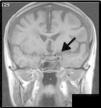

En un plano sagital de la resonancia magnética en T1 (fig. 4) se observó una imagen quística con realce en anillo, expansiva en el seno esfenoidal, la cual se confirmó en el plano coronal (fig. 5), asociado a un realce de las vainas meníngeas de la pared del seno cavernoso izquierdo y afección de estructuras neurovasculares causada por efecto de masa e inflamación.

Los hallazgos radiográficos característicos son demostrados a menudo mediante tomografía axial computarizada como una lesión expansiva llena de líquido mucoide de densidad homogénea delimitada por una seudocápsula y no por el límite óseo que en ocasiones ya no existe debido a la erosión. Al aplicarse medio de contraste, esta pared acumula en forma anormal el contraste y el líquido interno de la lesión no muestra cambios. En la resonancia magnética se observa una señal de baja intensidad en las secuencias T1 y alta intensidad en T2, debido al gran contenido líquido del mucocele, pudiendo predecir la cronicidad de la lesión cuando en ambas secuencias se observa una señal de intensidad media a alta por aumento de material proteinaceo en el interior de la lesión. Asimismo la resonancia es útil para realizar diagnóstico diferencial con lesiones malignas o de comportamiento atípico9.